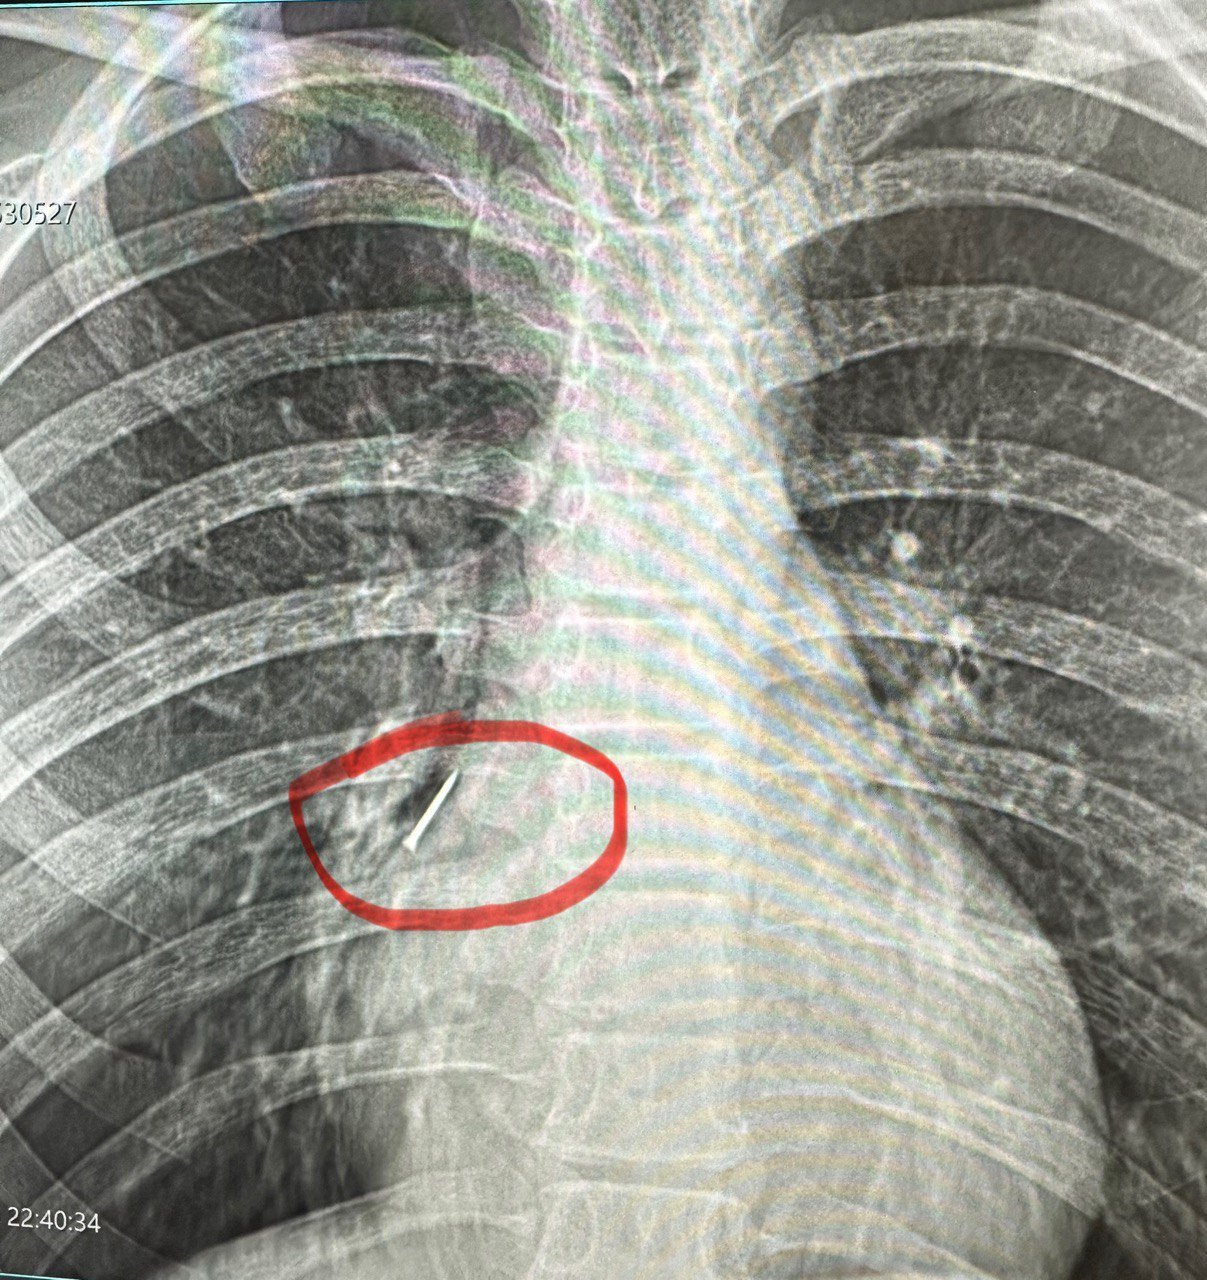

Як розповідає лікар-ендоскопіст та хірург дитячий Олександр Сльозко, проковтування монет дітьми – поширене явище. Такі випадки трапляються регулярно, подекуди й до 10 на тиждень. У квітні лікарям також довелося ендоскопічно діставати з бронхів підлітків цвях та канцелярську кнопку, а зі стравоходу дворічної дитини – натільний хрестик.